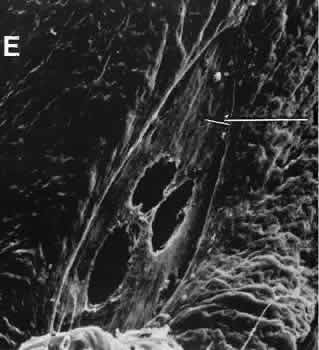

Fig. 10. Scanning electron micrograph of the posterior surface of the iris in a case of angle closure glaucoma treated with argon laser iridotomy. Centrally, there are three areas of penetration of iris tissue. Iris pigment epithelium has been lost for a considerable distance from the actual opening (arrow). Normal iris pigment epithelium is present peripherally.